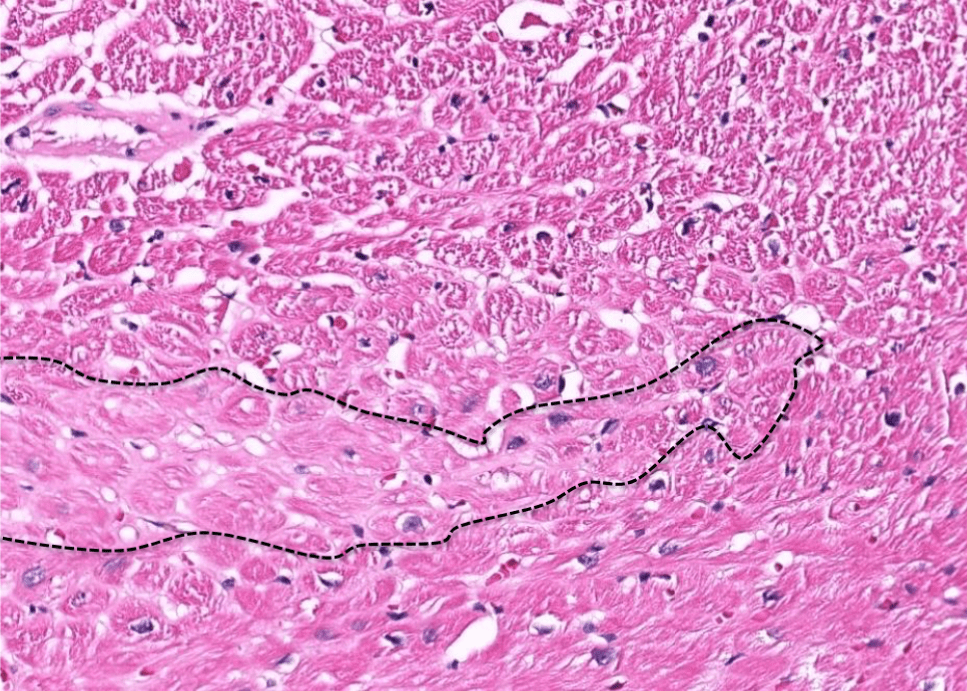

breast cancer

dyslipidemia

hepatocellular carcinoma